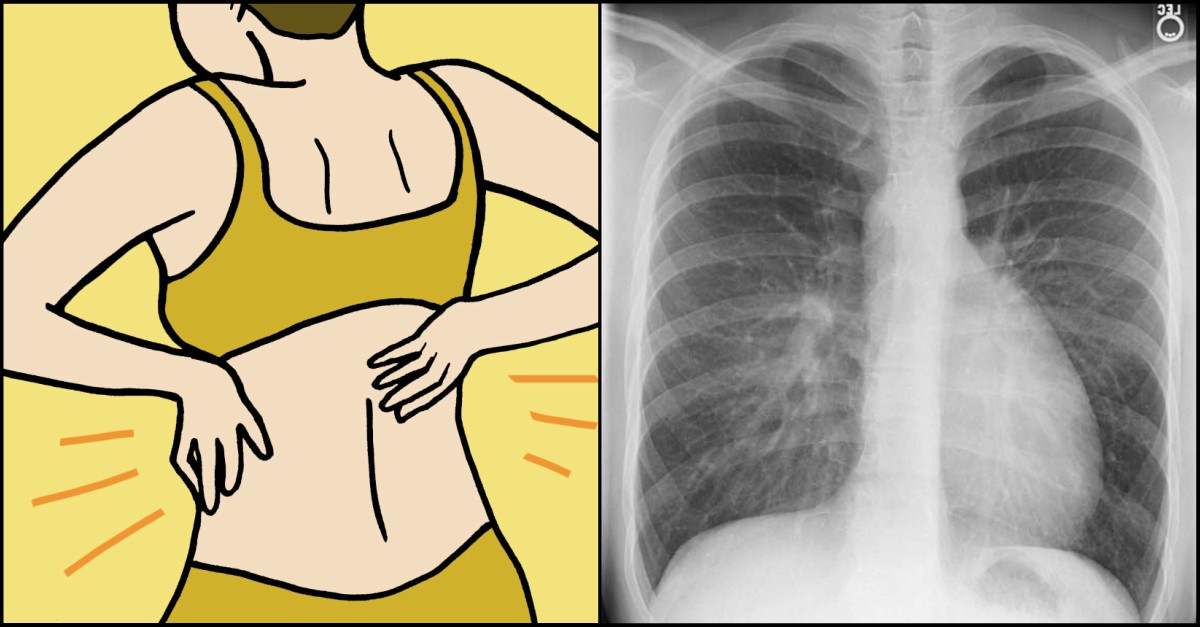

Ongoing abdominal pain or discomfort — including gas, indigestion, pressure, bloating and cramps — can signal ovarian or endometrial cancer. Common cancer symptoms in women the types that affect women most are breast, lung, and colorectal cancer. However, premenopausal women should be careful not to mistake symptoms of rectal cancer with menstrual issues. Bladder cancers that have grown large or have spread to other parts of the body can sometimes cause other symptoms, such as: When they do occur, signs of colon cancer in women tend to be the same as those seen in men, and can include:

According to the american cancer society, about 53,990 new cases of thyroid cancer in the u.s. The symptoms of lung cancer in women are sometimes different than in men, largely because both sexes tend to get different types of lung cancer. Metastases to bones can cause bone pain, back pain, chest pain, or shoulder pain. Blood in the urine (hematuria). Many women feel bloated from time to time, particularly due to hormonal changes during their menstrual cycle. Abnormal vaginal bleeding or discharge is common on all gynecologic cancers except vulvar cancer. These symptoms are linked to cervical cancer, uterine cancer, and ovarian cancer. Common cancer symptoms in women the types that affect women most are breast, lung, and colorectal cancer. Although it is easy to distinguish between some colorectal and gynecological symptoms, such as bleeding (rectal vs. However, premenopausal women should be careful not to mistake symptoms of rectal cancer with menstrual issues. This may be because cancer cells use up much of the body's energy supply. When cancer starts in a woman's reproductive organs, it is called gynecologic cancer. Hpv and cancer symptoms depending on the type of hpv a female has, they will present with different symptoms.

Vaginal itching or burning, back or abdominal pain, being tired all the time, having to pass urine very. The symptoms of lung cancer in women are sometimes different than in men, largely because both sexes tend to get different types of lung cancer. This pressure causes some of the signs and symptoms of cancer. As a woman, your lifetime odds of getting it are only one in 154, according to the american cancer society.that said, it can. Cancer is a disease in which cells in the body grow out of control. Appetite changes may be symptoms of ovarian cancer or other cancers not related to the reproductive system. They note that ovarian cancer accounts for more deaths than any other cancer of the female. Feeling full too quickly or difficulty eating, bloating, and abdominal or back pain are common only for ovarian cancer. However, premenopausal women should be careful not to mistake symptoms of rectal cancer with menstrual issues. This may be because cancer cells use up much of the body's energy supply. Blood in the urine (hematuria). Metastases to bones can cause bone pain, back pain, chest pain, or shoulder pain. Many women feel bloated from time to time, particularly due to hormonal changes during their menstrual cycle.